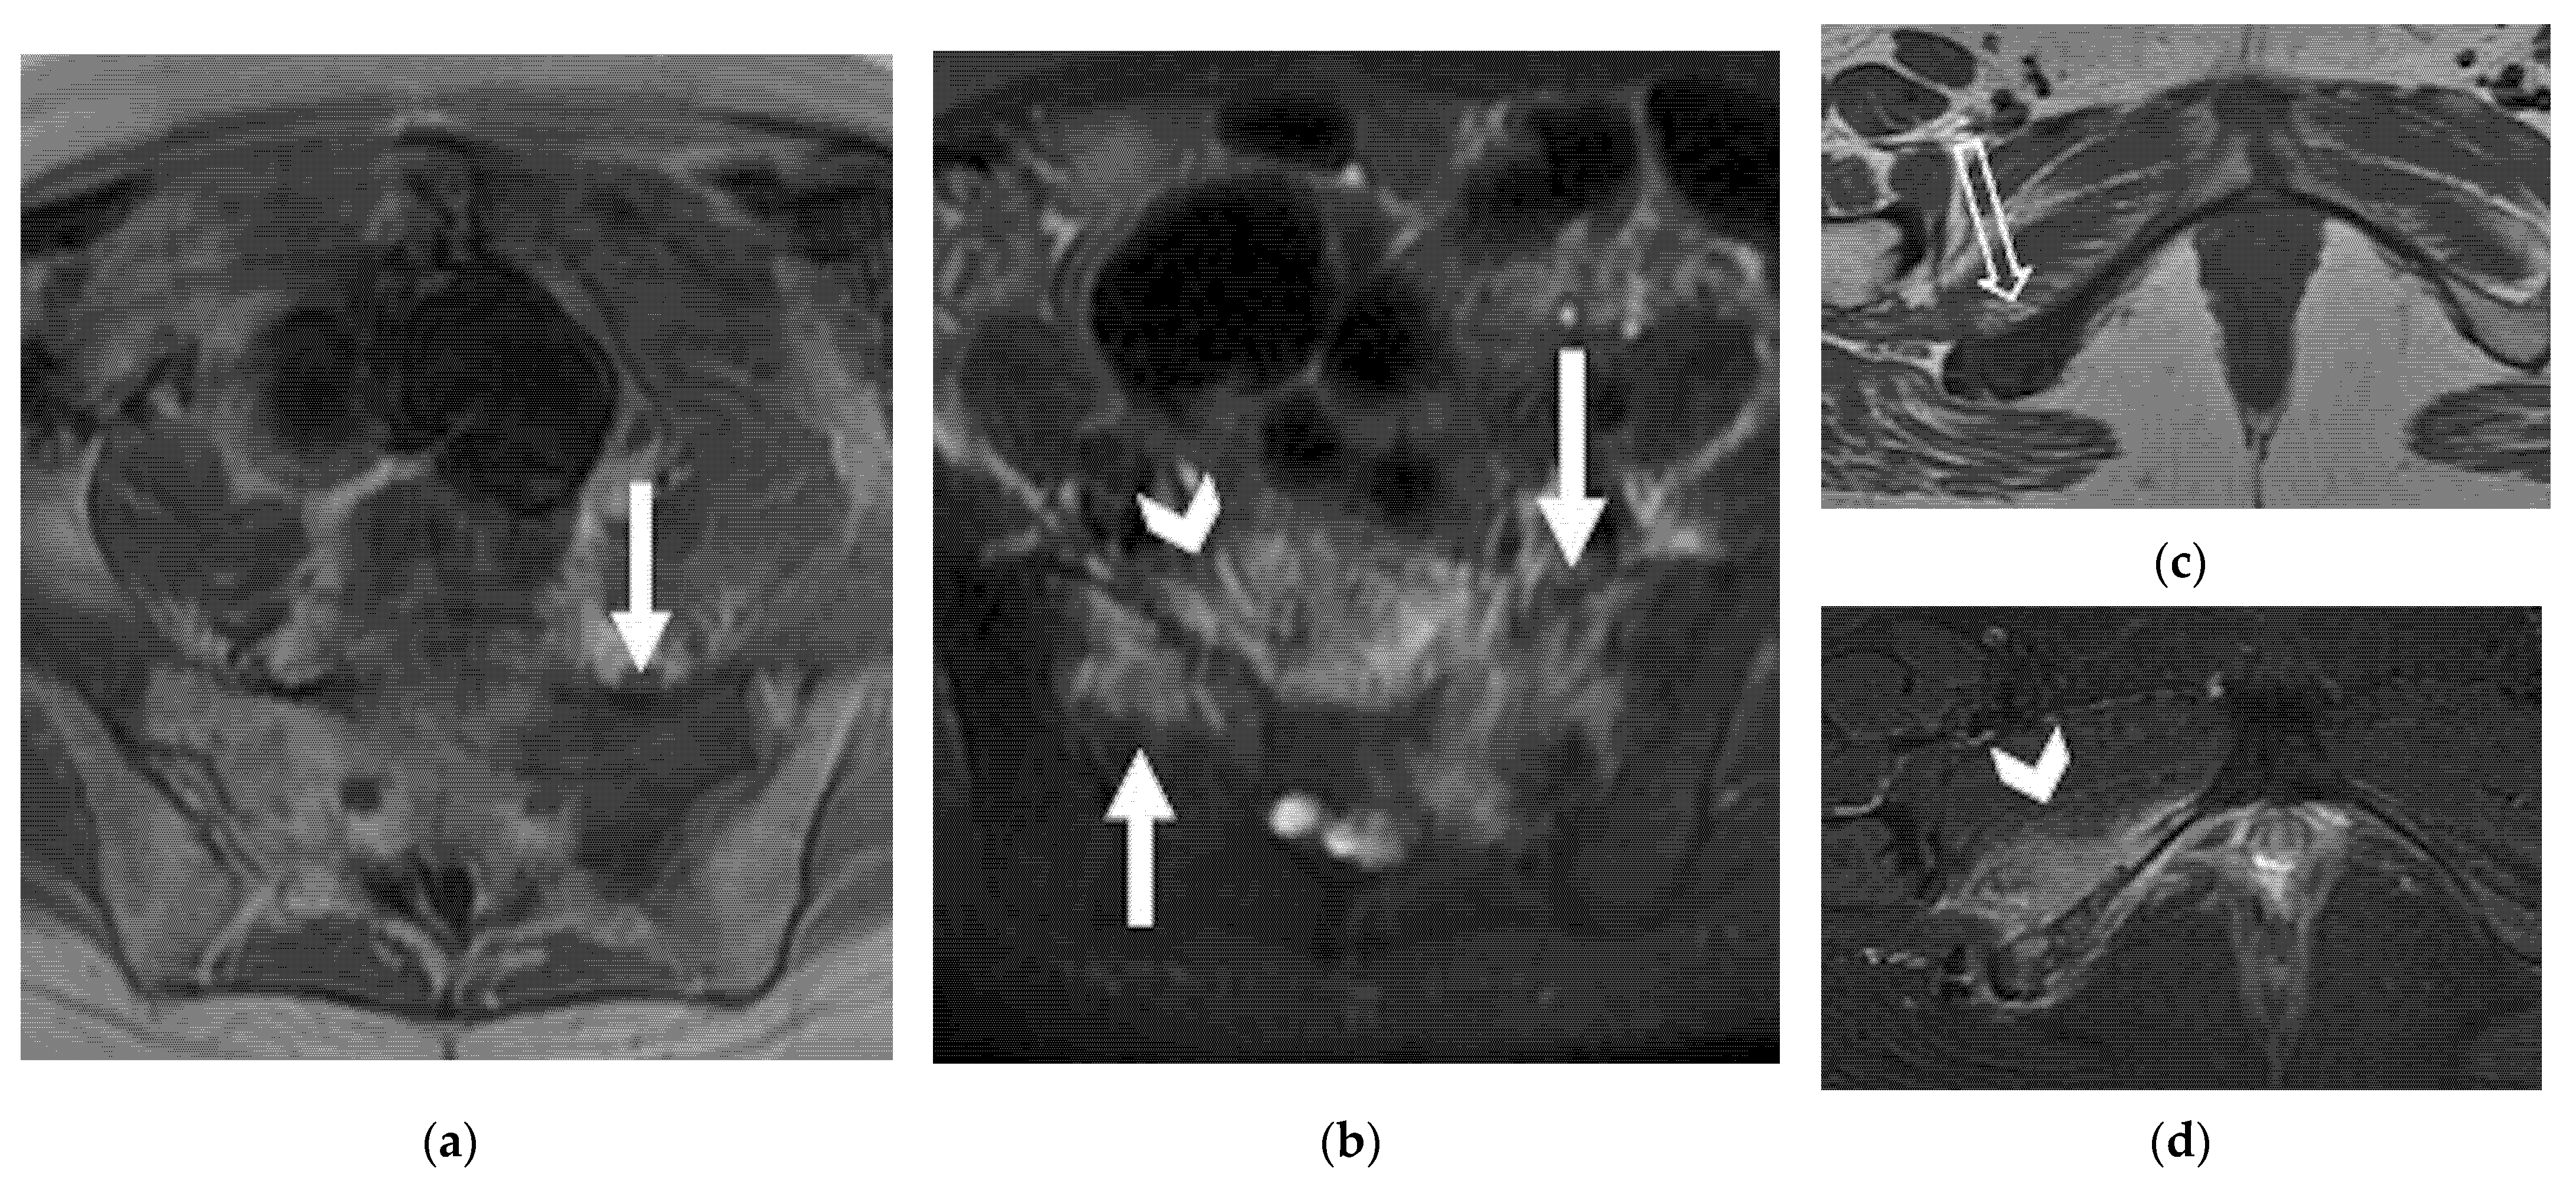

4.2.3. Lateral

| Lateral Pelvic sidewall ![]() | Pelvic sidewall recurrence is defined as a tumor extending within 3 mm and abutting the obturator internus or piriformis muscles with concomitant loss of fat planes. Other findings include:

|